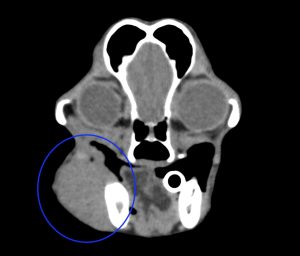

今回治療させていただいたワンちゃんは、口の奥に出来物が見つかったとのことで来院され、頬粘膜〜下顎の歯肉腫瘤を生検したところ、メラノーマと診断されました。

腫瘍の増殖スピードが速く、日に日に大きくなっていき、このままでは食べられなくなる可能性がありました。

手術は、腫瘍に片側下顎骨の大部分をつけて切除しました。また、下顎リンパ節、内側咽頭後リンパ節も切除しました。病理検査では、腫瘍は取り切れており、リンパ節転移もなしとの結果でした。